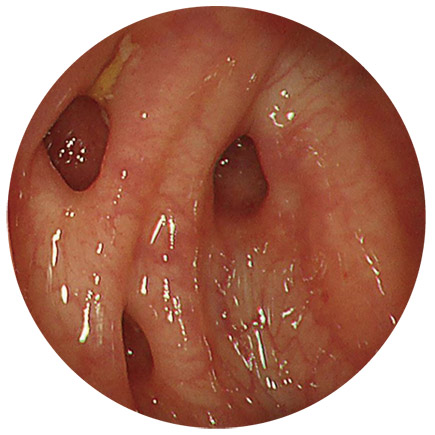

憩室

これらの病気を判別するのに必要な検査が、大腸内視鏡検査(大腸カメラ)になります。